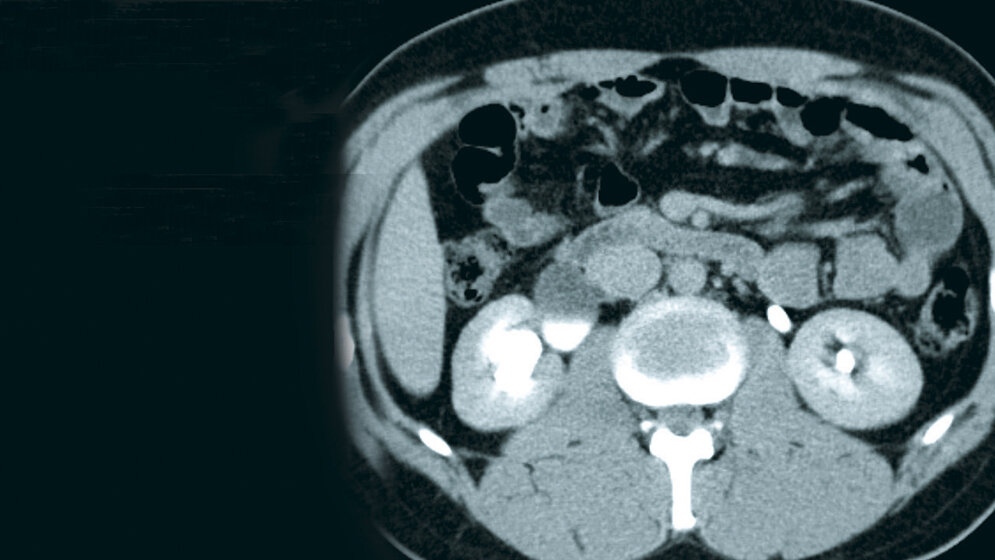

Die urogenitale Dysfunktion wird bei zahlreichen, insbesondere urologischen und neurologischen Erkrankungen beschrieben. Der Morbus Parkinson kann eine Ursache sein. Männliches Geschlecht, Fettleibigkeit und ein Alter über 75 Jahren sind Risikofaktoren für eine Nephrolithiasis, ebenso hämatologische Malignome, endokrine Störungen, Autoimmun- und entzündliche Darmerkrankungen, Osteoporose, Hypertonie, metabolisches Syndrom und Gefäßerkrankungen.

Schlüsselwörter: LWS, CT, MRT, Harnabflussstörung

Urogenital dysfunction is commonly reported in many, especially urologic and neurologic diseases. Parkinson’s disease may be one reason. Male gender, obesity and age more than 75 years might be independent risk factors for the development of nephrolithiasis, also hematologic malignancies, endocrine disorders, autoimmune diseases, inflammatory bowel diseases, bone loss, hypertension, metabolic syndrome and vascular diseases.

Keywords: Lumbar spine, CT, MRI, urodynamic disorder